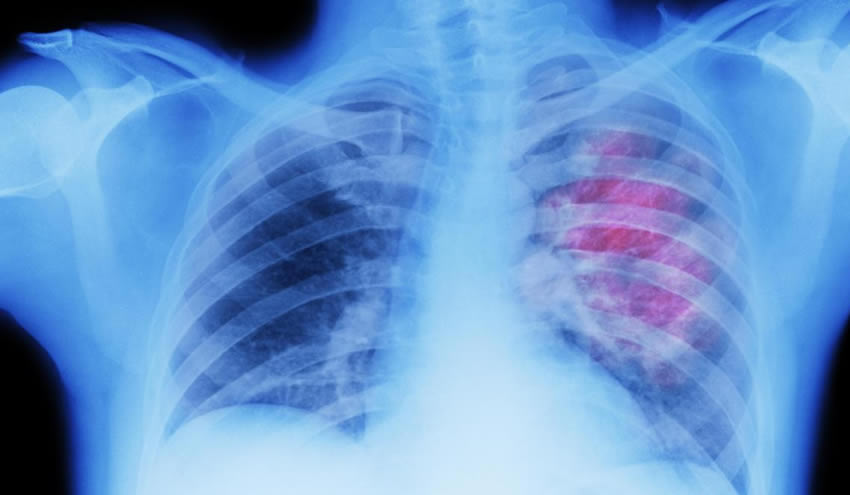

İngiltere Ulusal Sağlık Servisi’nin (NHS) yaptığı açıklamada, son teknoloji bir ürün olan ‘Sotorasib’ adlı ilacın, kanser tedavisi çalışmalarından önemli bir gelişme sağlayacağı belirtildi. ‘Ölüm Yıldızı’ adlı verilen mutasyonla akciğer kanserindeki tümör büyümesini durduran ‘devrim’ niteliğindeki bir ilaç, ilk kez Avrupa’daki hastalara verilecek.

Tablet olarak alınan ilaç, kanser tümörlerinin büyümesini durduruyor. Klinik çalışmalara göre, söz konusu ilacın akciğer kanserinin büyümesini 7 ay boyunca durdurduğu kanıtlandı.